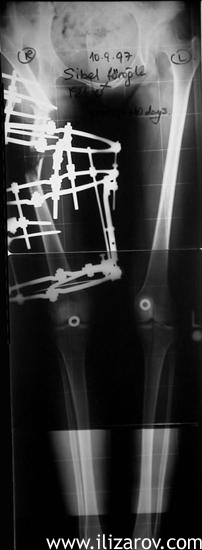

Figure 4. Anteroposterior orthoroentgenogram during treatment